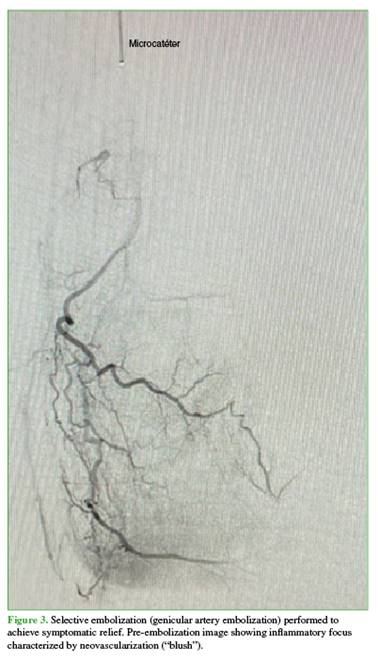

A 68-year-old male surgeon presented with degenerative joint disease and symptomatic genu varum (Figure 1).

Recently, he had to increase his analgesic medication and limit walking.

In previous consultations, intra-articular hyaluronic acid injection and prosthetic arthroplasty had been proposed.

At the time of evaluation, the patient reported having declined both options: a) he refused injection therapy because of progressive malalignment of the knee, and b) he was not yet willing to undergo prosthetic arthroplasty, as he did not perceive a significant limitation in his daily or professional activities.

Selective arterial embolization was therefore proposed (Figure 2).